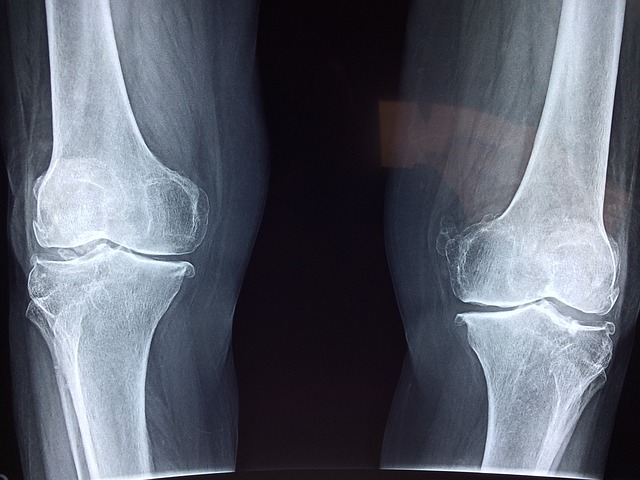

콘드로이친 연골.

⦁ 관절에 연골은 관절이 받는 하중을 흡수하고 움직임을 부드럽게 만들어주는 역할을 합니다.

⦁ 관절의 사용향이 많아지면 연골이 마모되고 손상이 되면서 관절을 보호해 주지 못하기 때문에 통

증이 발생하게 됩니다.